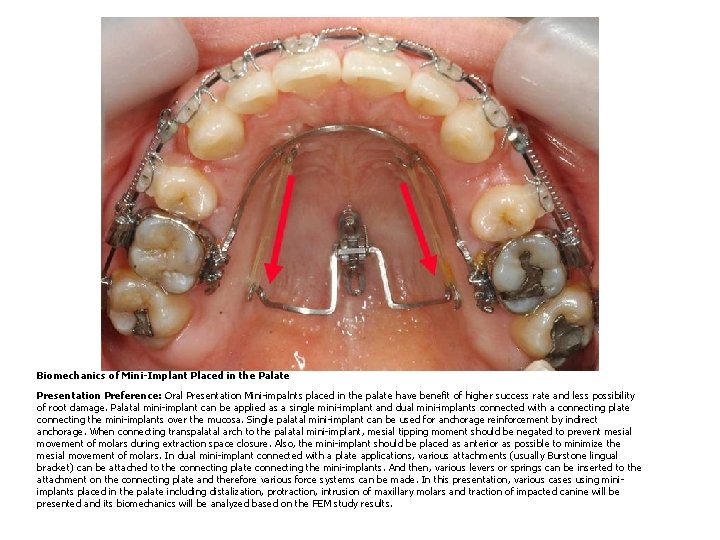

Biomechanics of Mini-Implant Placed in the Palate Presentation Preference: Oral Presentation Mini-impalnts placed in the palate have benefit of higher success rate and less possibility of root damage. Palatal mini-implant can be applied as a single mini-implant and dual mini-implants connected with a connecting plate connecting the mini-implants over the mucosa. Single palatal mini-implant can be used for anchorage reinforcement by indirect anchorage. When connecting transpalatal arch to the palatal mini-implant, mesial tipping moment should be negated to prevent mesial movement of molars during extraction space closure. Also, the mini-implant should be placed as anterior as possible to minimize the mesial movement of molars. In dual mini-implant connected with a plate applications, various attachments (usually Burstone lingual bracket) can be attached to the connecting plate connecting the mini-implants. And then, various levers or springs can be inserted to the attachment on the connecting plate and therefore various force systems can be made. In this presentation, various cases using miniimplants placed in the palate including distalization, protraction, intrusion of maxillary molars and traction of impacted canine will be presented and its biomechanics will be analyzed based on the FEM study results.